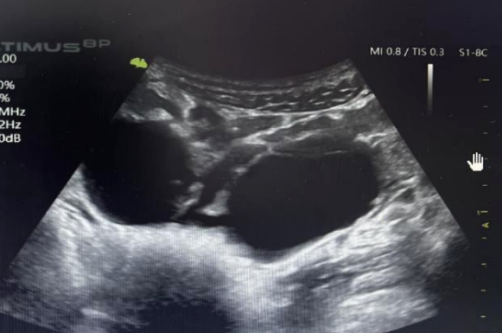

消化内镜下注射聚桂醇原液治疗肝囊肿

囊肿性疾病聚桂醇硬化治疗四例